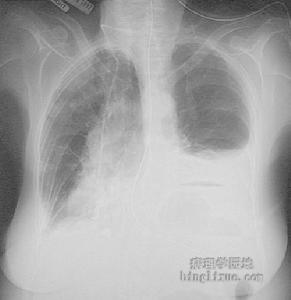

1.胸部X線所見雖不具有診斷意義但很具有特徵性。如果出現邊界不清小結節影(2~10mm)、網狀結節影上野囊狀變或蜂窩肺、肺容積不變以及肋膈角不受累等聯合表現則對本病診斷具有高度特異性。典型的網狀結節影見於中上野,與病理結果相一致。肺總量多正常,但也可見肺過度充氣和肺容積縮小。除LCH外,淋巴平滑肌瘤病結節性硬化症慢性過敏性肺(泡)炎、Ⅲ期結節病、縮窄性細支氣管炎以及任何有肺氣腫的ILD均可表現為肺容積增大。LCH的影像學標誌為小囊腫和小結節影,偶爾可見粟粒樣病變。LCH的肺門或縱隔淋巴結腫大罕見,如有腫大第二診斷應考慮惡性腫瘤。本病的原發胸膜受累少見,胸膜肥厚常是由於治療氣胸所致。骨損害可以發生於任何骨骼,包括肋骨。極罕見的情況下,病人只表現為孤立的肺部結節而在活檢中證實為LCH。

2.胸部的CT檢查當一年輕吸菸者,同時出現中上野分布為主的多發囊腫和小結節影時非常具有特徵性,可以考慮診斷LCH。小結節界限可以清晰或不清,偶爾可以較大而且形態奇異,進展期可見蜂窩肺改變。系列CT掃描可以觀察到,在一段時間內結節影經歷空洞變並向囊性變進展的過程。形成囊腫的程度在常規X線上常被低估,可以解釋在薄層CT常規套用以前文獻報告的很多所謂“自然緩解”病例。